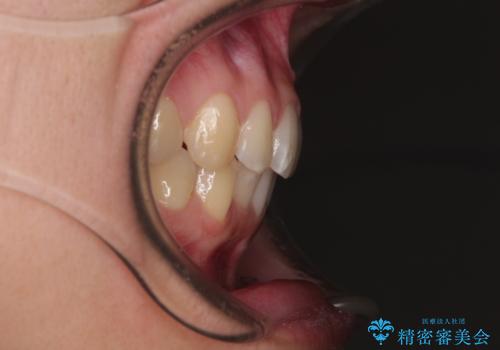

- 上下のクロスバイトと前歯のデコボコを気にして来院された患者様です。

インビザラインを用い、IPR(歯と歯の間を削る)と歯列全体を拡大させることで、歯並びを整えていくこととしました。

下の歯が隠れてしまうほどでしたが、深い咬み合わせも改善され、顎への負担も軽減されました。